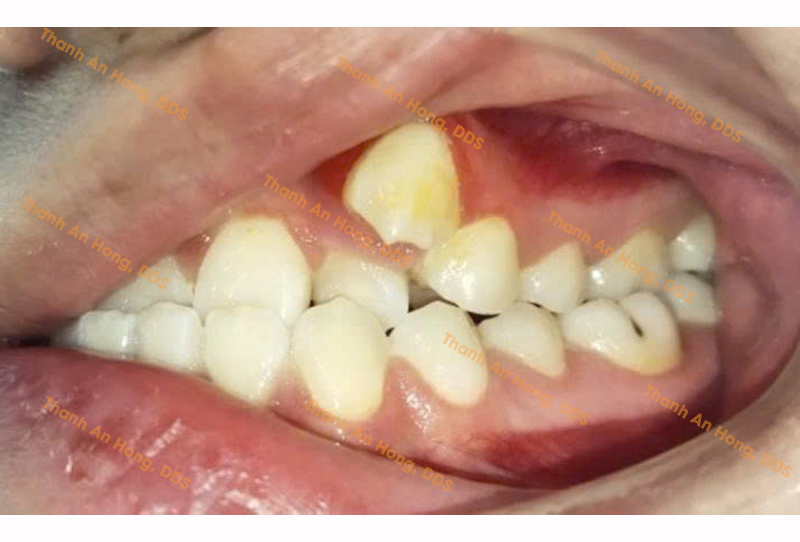

HÌNH ẢNH THỰC TẾ

Chỉnh mắc cài giảm hô